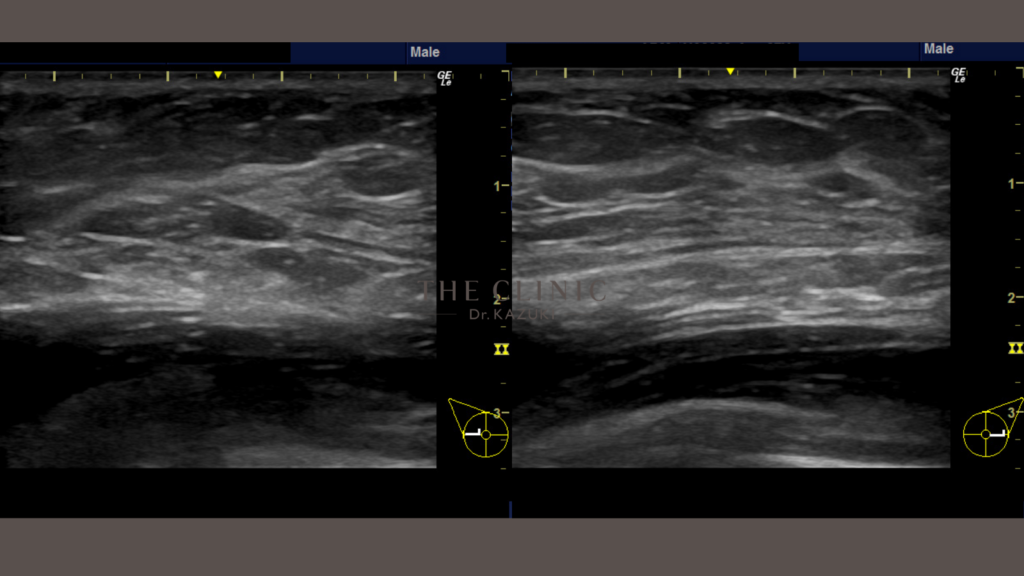

術前のエコーで、乳腺の厚みも確認されましたが、デザインされたベイザー脂肪吸引によるボリュームダウンと皮膚引き締まりにより、胸のふくらみが解消されました。「脇肉前」も一緒に吸引したことにより、脇前の脂肪の膨らみも解消されています。

術後の完成目安は6カ月です。この時期には拘縮(硬さ)も落ち着き、自然な質感に仕上がります。よりボリュームダウンを図る場合には、乳腺切除が必要なケースもあります。「脂肪」が主因であれば、吸引のみで胸のふくらみの解消が可能です。まずはエコー検査で、ご自身のタイプを確認することをお勧めします。